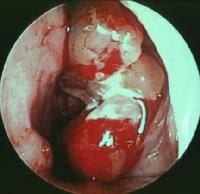

✔ Sialoendoskopi: Küçük kamera ile doğrudan kanal içine bakılarak taşın yerinin tespit edilmesi ve tedavide kullanılması için de tercih edilebilir.

Sialoendoskopi: Küçük bir kamera ve aletlerle taşın kanaldan çıkarılması

Şok dalga litotripsisi: Taşları kırarak küçük parçalar hâline getirip dışarı çıkmasını sağlama

Sialoendoskopi (hem tanı hem tedavi)

Sialoendoskopik çıkarma